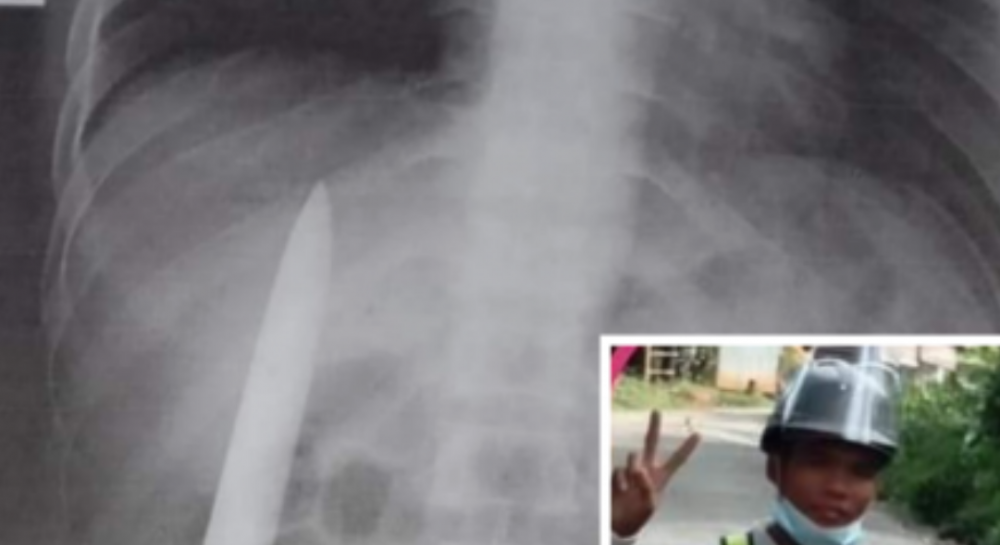

Оскари с президентом находят упавший в озеро самолет и прячутся там. Хазар находит их, но беглецы успевают катапультироваться. С воздуха на вертолете охоту на них ведет Моррис, но юный лапландец, летя на катапульте, выстреливает в него из лука. Стрела чуть-чуть задевает злодея, но этого оказывается достаточно, чтобы старый осколок пули, давно сидевший в груди Морриса, сдвинулся и поразил сердце. Он мгновенно умирает.